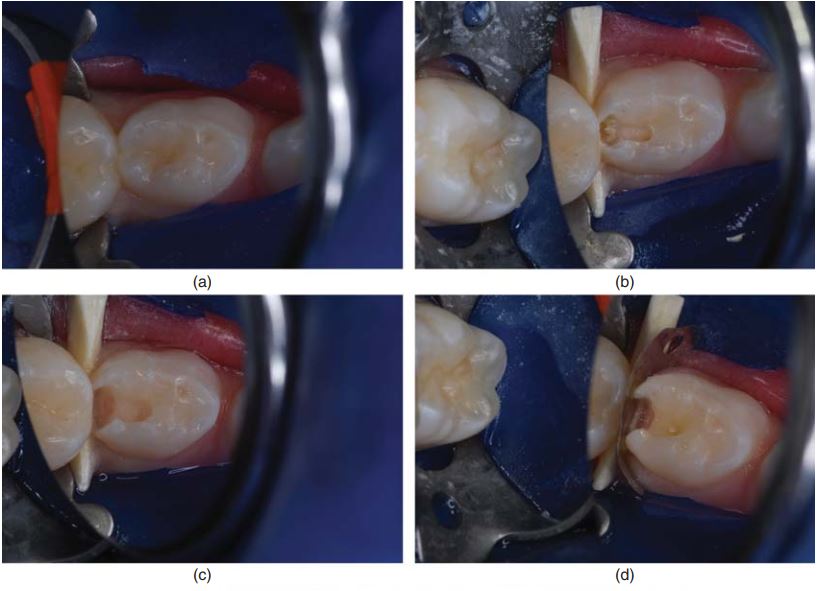

Hình 4.2a đến 4.4g minh họa trám răng cối sữa bằng RMGI.

Vật liệu glass ionomer phối hợp nhựa (RMGI) được khuyên chỉ định cho xoang I, II và V, vì nó có những ưu điểm của glass ionomer cổ điển. Việc phối hợp thêm nhựa giúp cải thiện nhiều đặc tính vật lí như kháng gãy, kháng mòn và tăng thẩm mĩ.

RMGI trùng hợp bằng đèn và bằng phản ứng hóa học giữa acid và base. Thế hệ vật liệu mới nhất hiện nay là “nano – ionomer” (Ketac Nano, 3M ESPE).

Trám răng bằng RMGI cũng cần cách li tốt, tuy nhiên nó ít gây nhạy cảm và thời gian làm việc ngắn hơn so với vật liệu composite. Đây là yêu cầu rất quan trọng khi điều trị răng trẻ em.